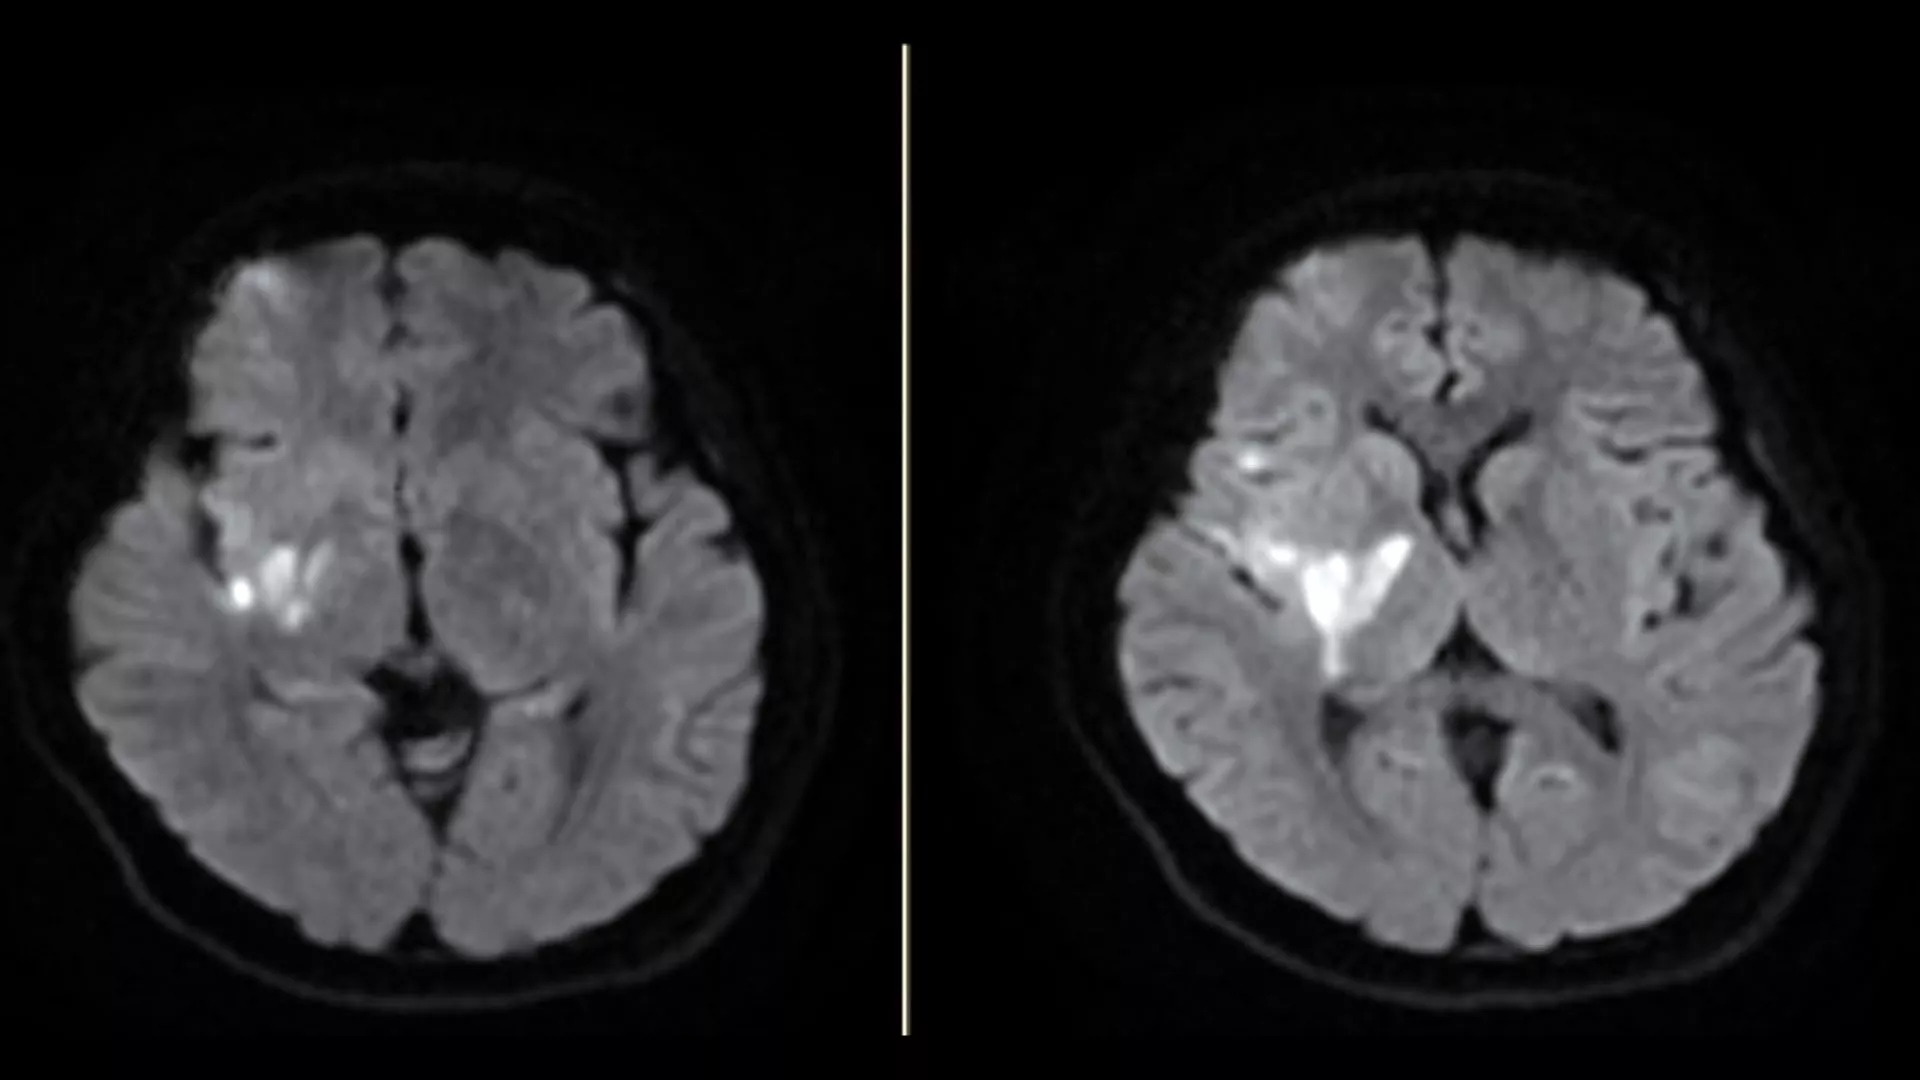

Tidak hanya di musim gugur dan musim dingin saja, di musim panas juga harus waspada terhadap stroke! Dokter mengatakan bahwa saat udara terlalu panas, keringat akan meningkat. Jika kadar air tubuh tidak diisi ulang tepat waktu, dehidrasi akan mudah terjadi dan bisa membuat kemungkinan terkena stroke meningkat secara signifikan. Menurut statistik Kementerian Kesehatan dan Kesejahteraan (MOHW), penyakit serebrovaskular ini menduduki peringkat lima dalam sepuluh besar penyebab kematian di Taiwan. Pada tahun 2022, penyakit ini merenggut 12.000 nyawa, yang berarti rata-rata satu orang meninggal karena penyakit serebrovaskular setiap 42 menit.

Dokter mengungkapkan bahwa selain angka kematian akibat stroke, kecacatan dan gejala sisa akibat stroke juga memberikan beban berat bagi pasien dan perawatannya. Namun, stroke sebenarnya bisa dicegah. Jika Anda atau anggota keluarga Anda memiliki tiga dari delapan faktor utama: tekanan darah tinggi, diabetes, kolesterol tinggi, denyut jantung tidak teratur, kurang olah raga, kelebihan berat badan, merokok, dan riwayat stroke, maka sudah termasuk dalam kelompok berisiko tinggi.